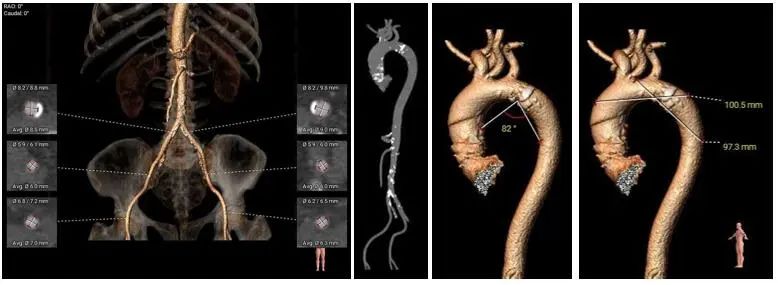

主动脉瓣环水平夹角47°,非横位心,主动脉弓角度及弓距可。

入路血管走形稍迂曲,主动脉弓,腹主动脉及左右髂总动脉有附壁钙化分布,血管内径可。

外周血管入路评估